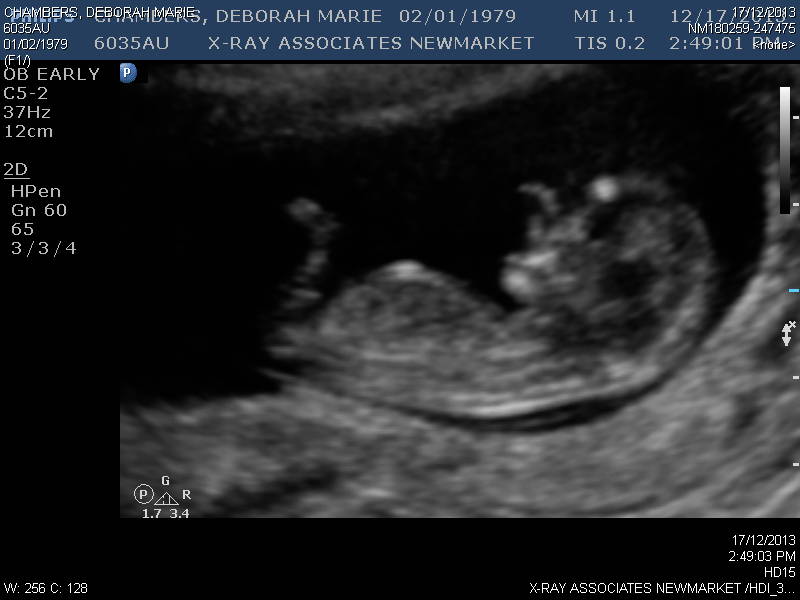

I have tired and tired and looked at so many sites tonight and my eyes hurt! I would love some guesses as to if this is a girl or a boy nub :)Attachment 15758Attachment 15760

Its not a very clear picture at all but I think boy! Going off the last shot as the first two I don't think the nub is visible at all in 1 and 2 looks cut off!

Sticking with rainbow. I think the third shows the best nub shot and it looks boyish to me.